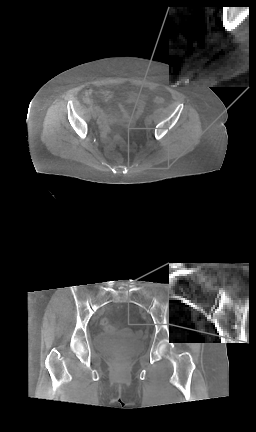

Refer to caption

(a)

(b)

(c)

(d)

Figure 4: (a) Axial (top) and coronal (bottom) slices of planning pelvice CT, HU range=(-400, 400) and (-150, 250) for ROI, (b) FDK (c) TV++ (d) LIRE++

We perform a proof-of-concept evaluation of LIRE++ on real CBCT pelvic data and compare it to the FDK baseline with U-net for scatter pre-correction and a proprietary TV++ method currently in use in our center. In addition to FDK we evaluate its calibrated version, where the HU values from FDK reconstruction all undergo a single affine transformation, which was determined by a linear regression matching central slices of the FDK reconstructions with the corresponding slices of planning CTs. To provide quantitative a comparison in terms of HU accuracy, we used planning CT and rigid registration.

The results are presented in Table 2. MAE in Hounsfield Units is measured in the central full field of view region. Additionally, we selected four spherical regions of interest between 2 and 4 cm in diameter, which are well aligned in planning and CBCT, and computed the mean HU intensities inside these regions to measure reproduction accuracy of various regions. The mean difference of these HU averages between planning CT and the reconstructions are given in Table 2 as well. Axial and coronal image slices are presented in Figure 4.

This comparison demonstrates that LIRE++ translates well to real CBCT pelvic data. Reconstruction given by LIRE++ is noticeably cleaner than the TV++ reconstruction, scatter artifacts in particular are well-suppressed. Field of view given by LIRE++ is slightly larger compared to TV++. We have measured an improvement in mean HU accuracy, however, due to anatomical differences such comparison can underestimate actual reconstruction quality. TV++, on the other hand, substantially outperforms a classical FDK method with deep-learning scatter precorrection and its calibrated version.